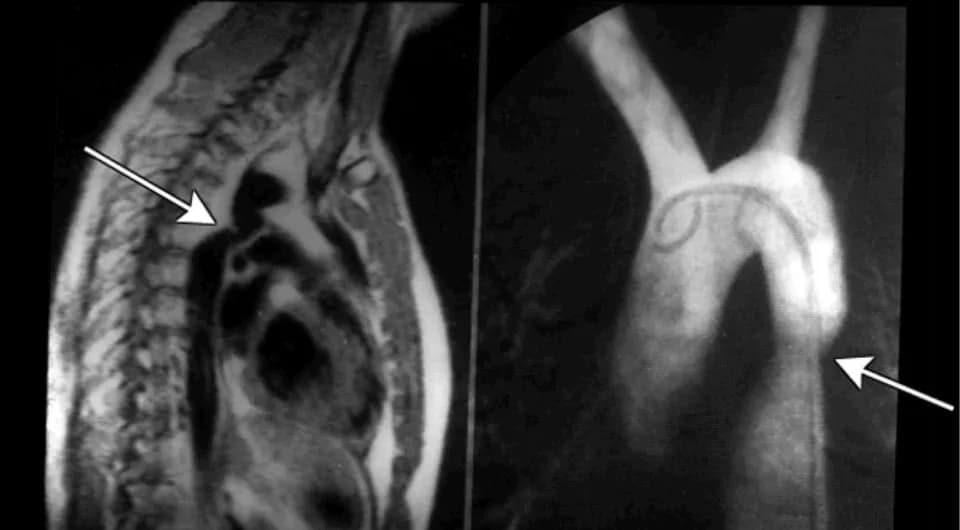

Siêu âm Doppler tim: Thường hữu ích ở trẻ nhỏ, ở người lớn thì khó đánh giá hơn. Trên siêu âm có thể xác định vị trí của chỗ hẹp, đo được chênh áp qua eo động mạch chủ, phát hiện các bất thường bẩm sinh phối hợp như van động mạch chủ hai lá van, tắc nghẽn đường ra thất trái, hẹp van hai lá…

Chụp cắt lớp vi tính động mạch chủ: Là phương tiện quyết định chẩn đoán hẹp eo động mạch chủ ở người lớn. Trên phim chụp xác định được vị trí, hình thái chỗ hẹp, các tuần hoàn bàng hệ và các tổn thương phối hợp.

Thông tim chẩn đoán: Đưa các dụng cụ qua đường mạch máu ngoại biên (động mạch đùi hoặc động mạch quay) để chụp chỗ hẹp và tuần hoàn bàng hệ. Hẹp eo động mạch chủ được chẩn đoán khi chênh áp trên 10mmHg giữa động mạch chủ lên và động mạch chủ xuống. Tuy nhiên chênh áp không phản ánh mức độ hẹp vì có thể ảnh hưởng bởi các tuần hoàn bàng hệ.

Chẩn đoán hẹp eo động mạch chủ dựa trên X-quang.